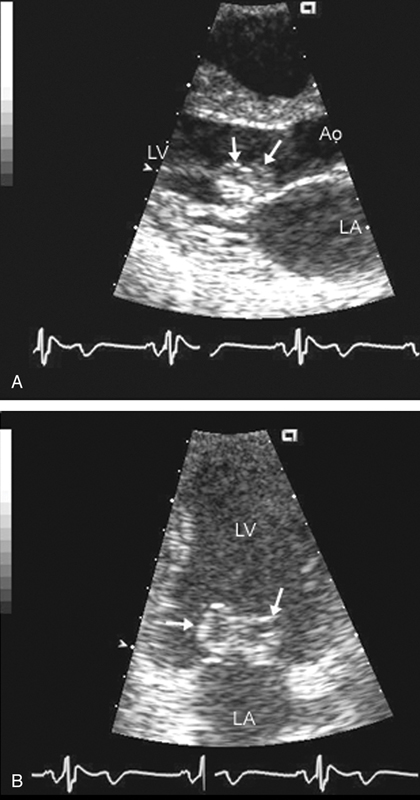

فحوصات تشخيصية لبعض امراض القلب والشرايين التاجية